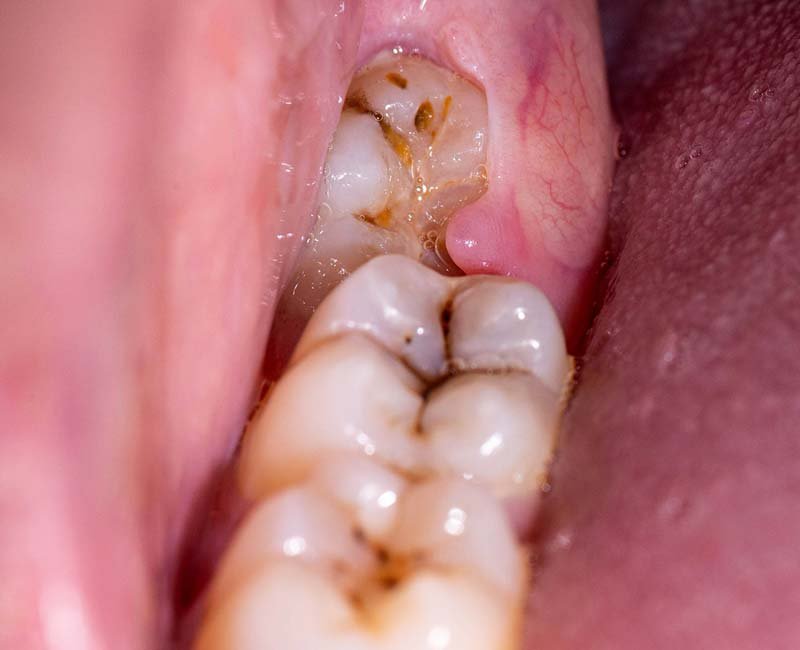

Do răng khôn mọc sau cùng mà vòm miệng của con người thường không có đủ chỗ để chúng mọc bình thường. Do đó, răng khôn mọc lệch, xô lẫn nhau, mọc chen chỗ các răng khác, dẫn đến sưng, đau đớn.

Có nhiều trường hợp gặp phải tình trạng những chiếc răng khôn mọc ngầm, mọc lệch không can thiệp kịp thời, khiến phần nướu răng sưng tấy, dễ tích đọng thức ăn gây hôi miệng, viêm nướu…

Răng khôn mọc còn có thể gây nhiều biến chứng như: viêm nhiễm, đau nhức khi bị mọc răng khôn. Răng khôn mọc lệch, mọc ngầm khiến bệnh nhân sưng, đau nhức trong miệng nên không thể nhai thức ăn.